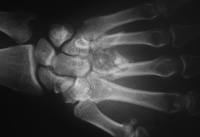

| Middle and ring

metacarpal base fractures with pulverized middle

metacarpal base. |